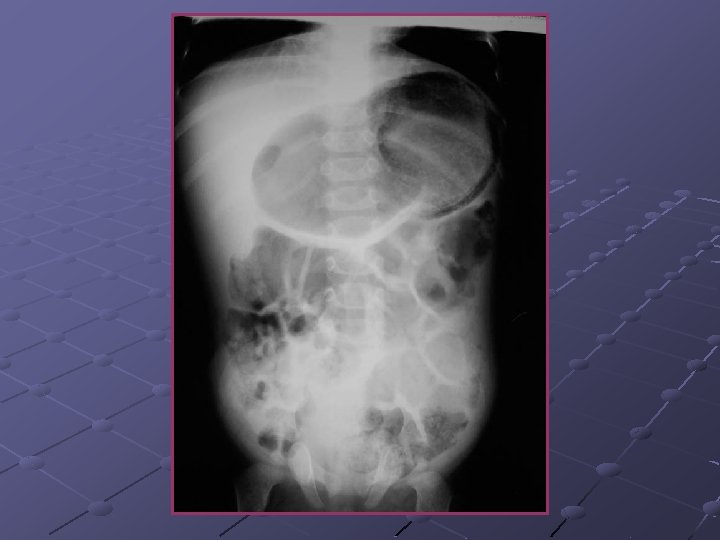

Cas n° 3 Garçon de 19 ans Pas d’antécédents particuliers Douleurs et distension abdominales, vomissements Examen distension diffuse, pas de signes de péritonite

« northern exposure sign » « coffee bean sign »

Volvulus du colon sigmoïde Cause fréquente de volvulus( segment long et mobile) ASP couché ( « coffee bean sign » ) pose le diagnostic dans 80% des cas Origine congénitale ou défaillance des moyens de fixité du colon ttt: décompression endoscopique suivie d’une résection élective